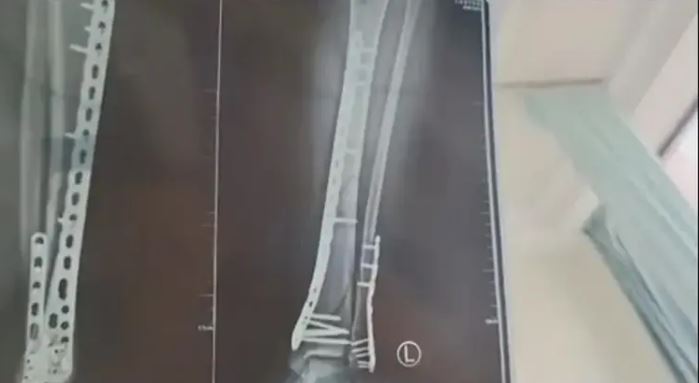

综合媒体报道,母亲节当天,兰州的武女士穿着一双7公分厚的洞洞鞋在下楼时不慎崴脚摔倒,由于鞋底设计较厚且脚掌中间有凹陷,导致她在下楼梯时脚部失去平衡,整个人向前扑倒,重力瞬间集中在腿上,造成了左腿粉碎性骨折。

武女士称,因为洞洞鞋的鞋底比较厚,脚掌中间又是凹进去的,自己下楼梯的时候正好踩到凹进去的地方,当时脚没有踩稳,整个人的重心往前扑,所有重力都集中在腿上,结果就骨折了。

武女士后来在网上发帖称,自己目前已做完手术在家休养,她特意提醒大家,穿增高鞋要注意。